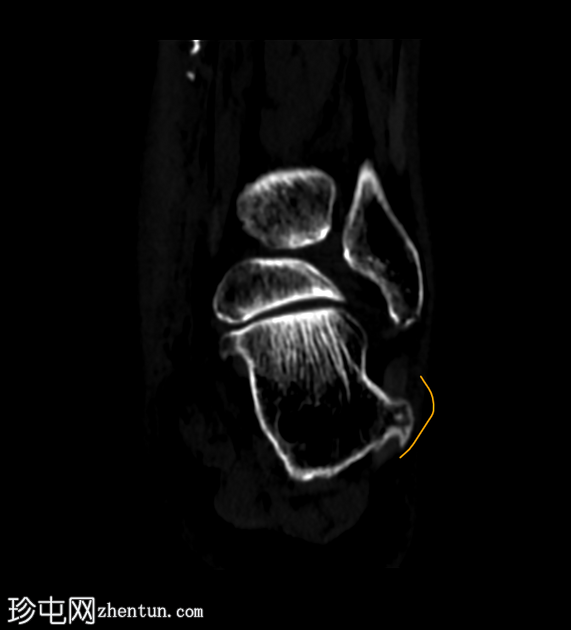

跟骨外侧

疼痛

。

年龄:65岁

性别:女

跟骨轴位CT

轴位

平扫

轴位骨窗